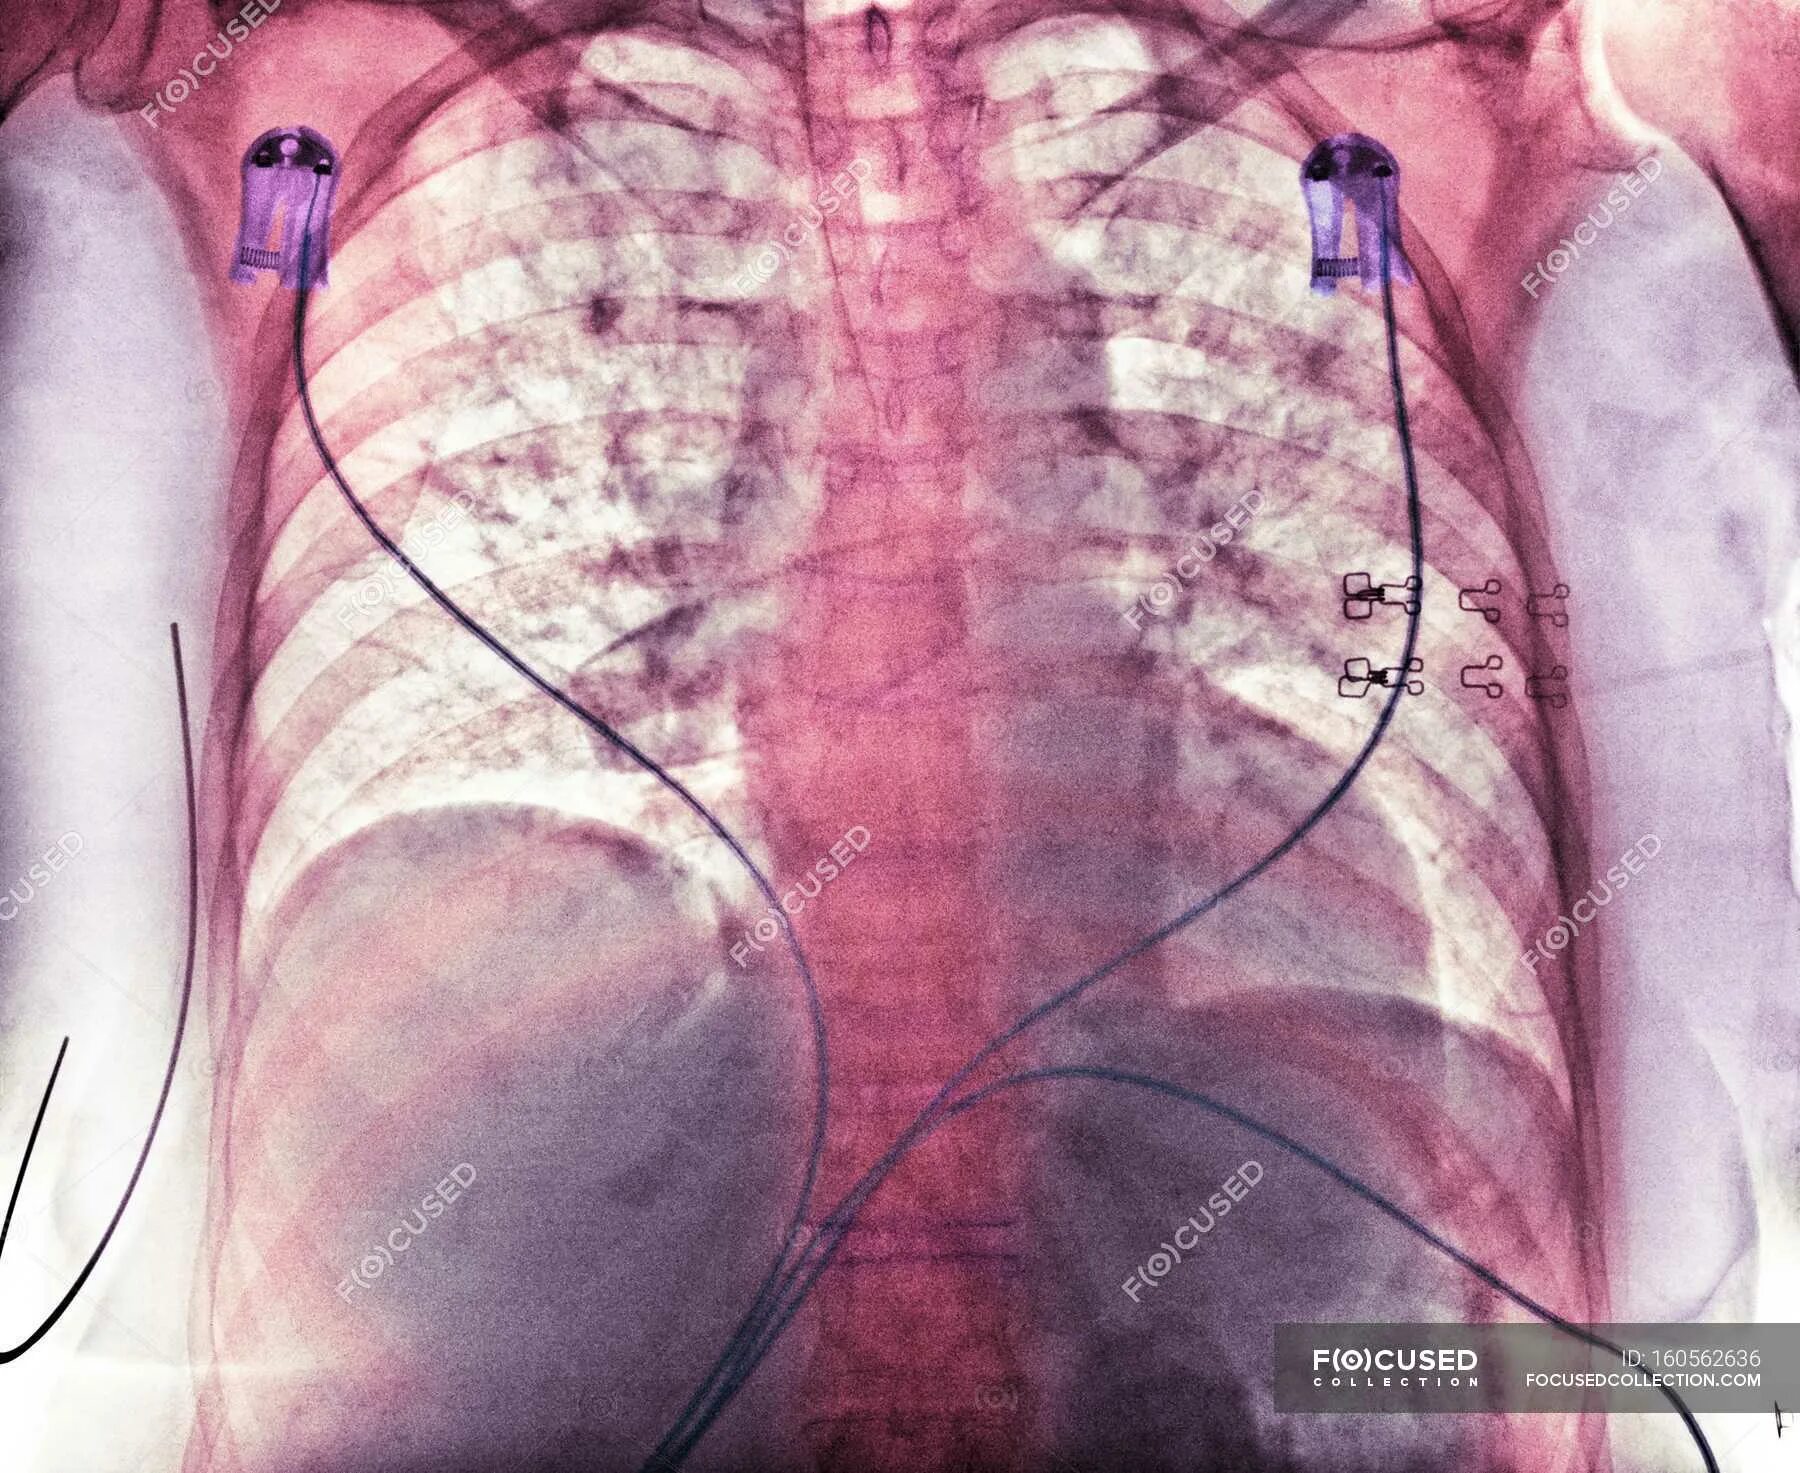

Синдром аспирации